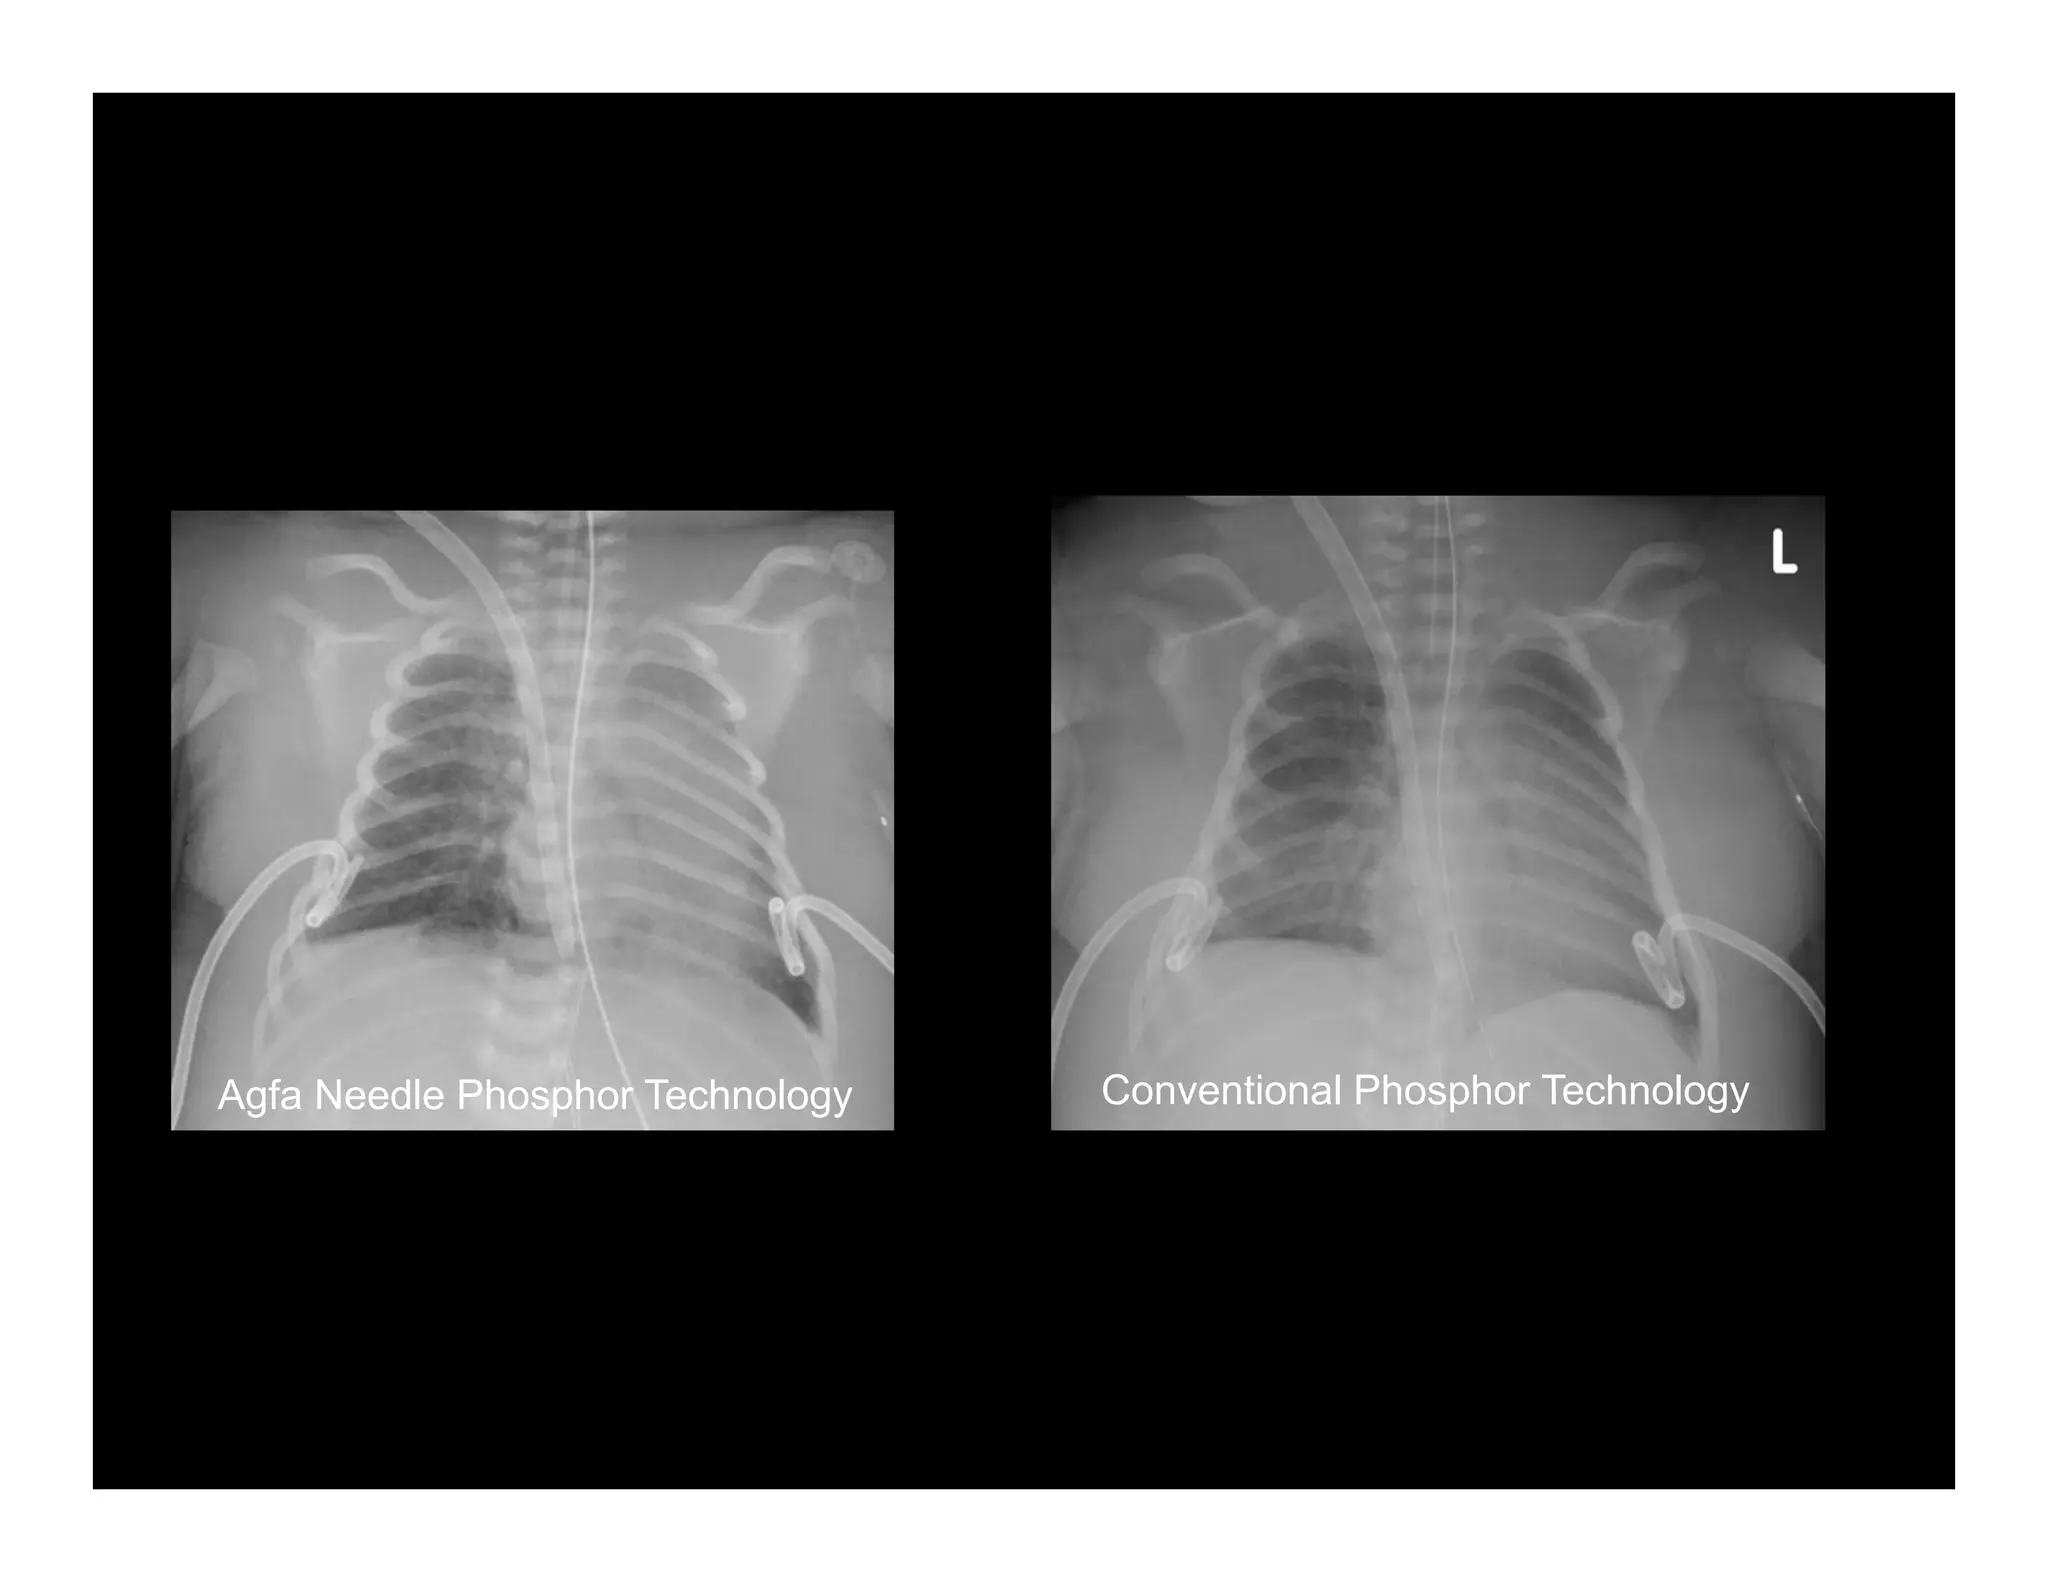

Agfa Needle Phosphor Technology                Conventional Phosphor Technology

Agfa Needle PhosphorTechnology Conventional Phosphor Technology Global D.I.R. Meeting Mortsel, February 21 – 23, 2011

Image Quality andDose Management Requires Advanced Technology How? Agfa HealthCare offers: With Cesium based Needle Phosphor Plates for CR and Cesium based DR Detector options – 20- 20-50% dose reduction is “achievable”! And, that is not simply our opinion… Global D.I.R. Meeting Mortsel, February 21 – 23, 2011